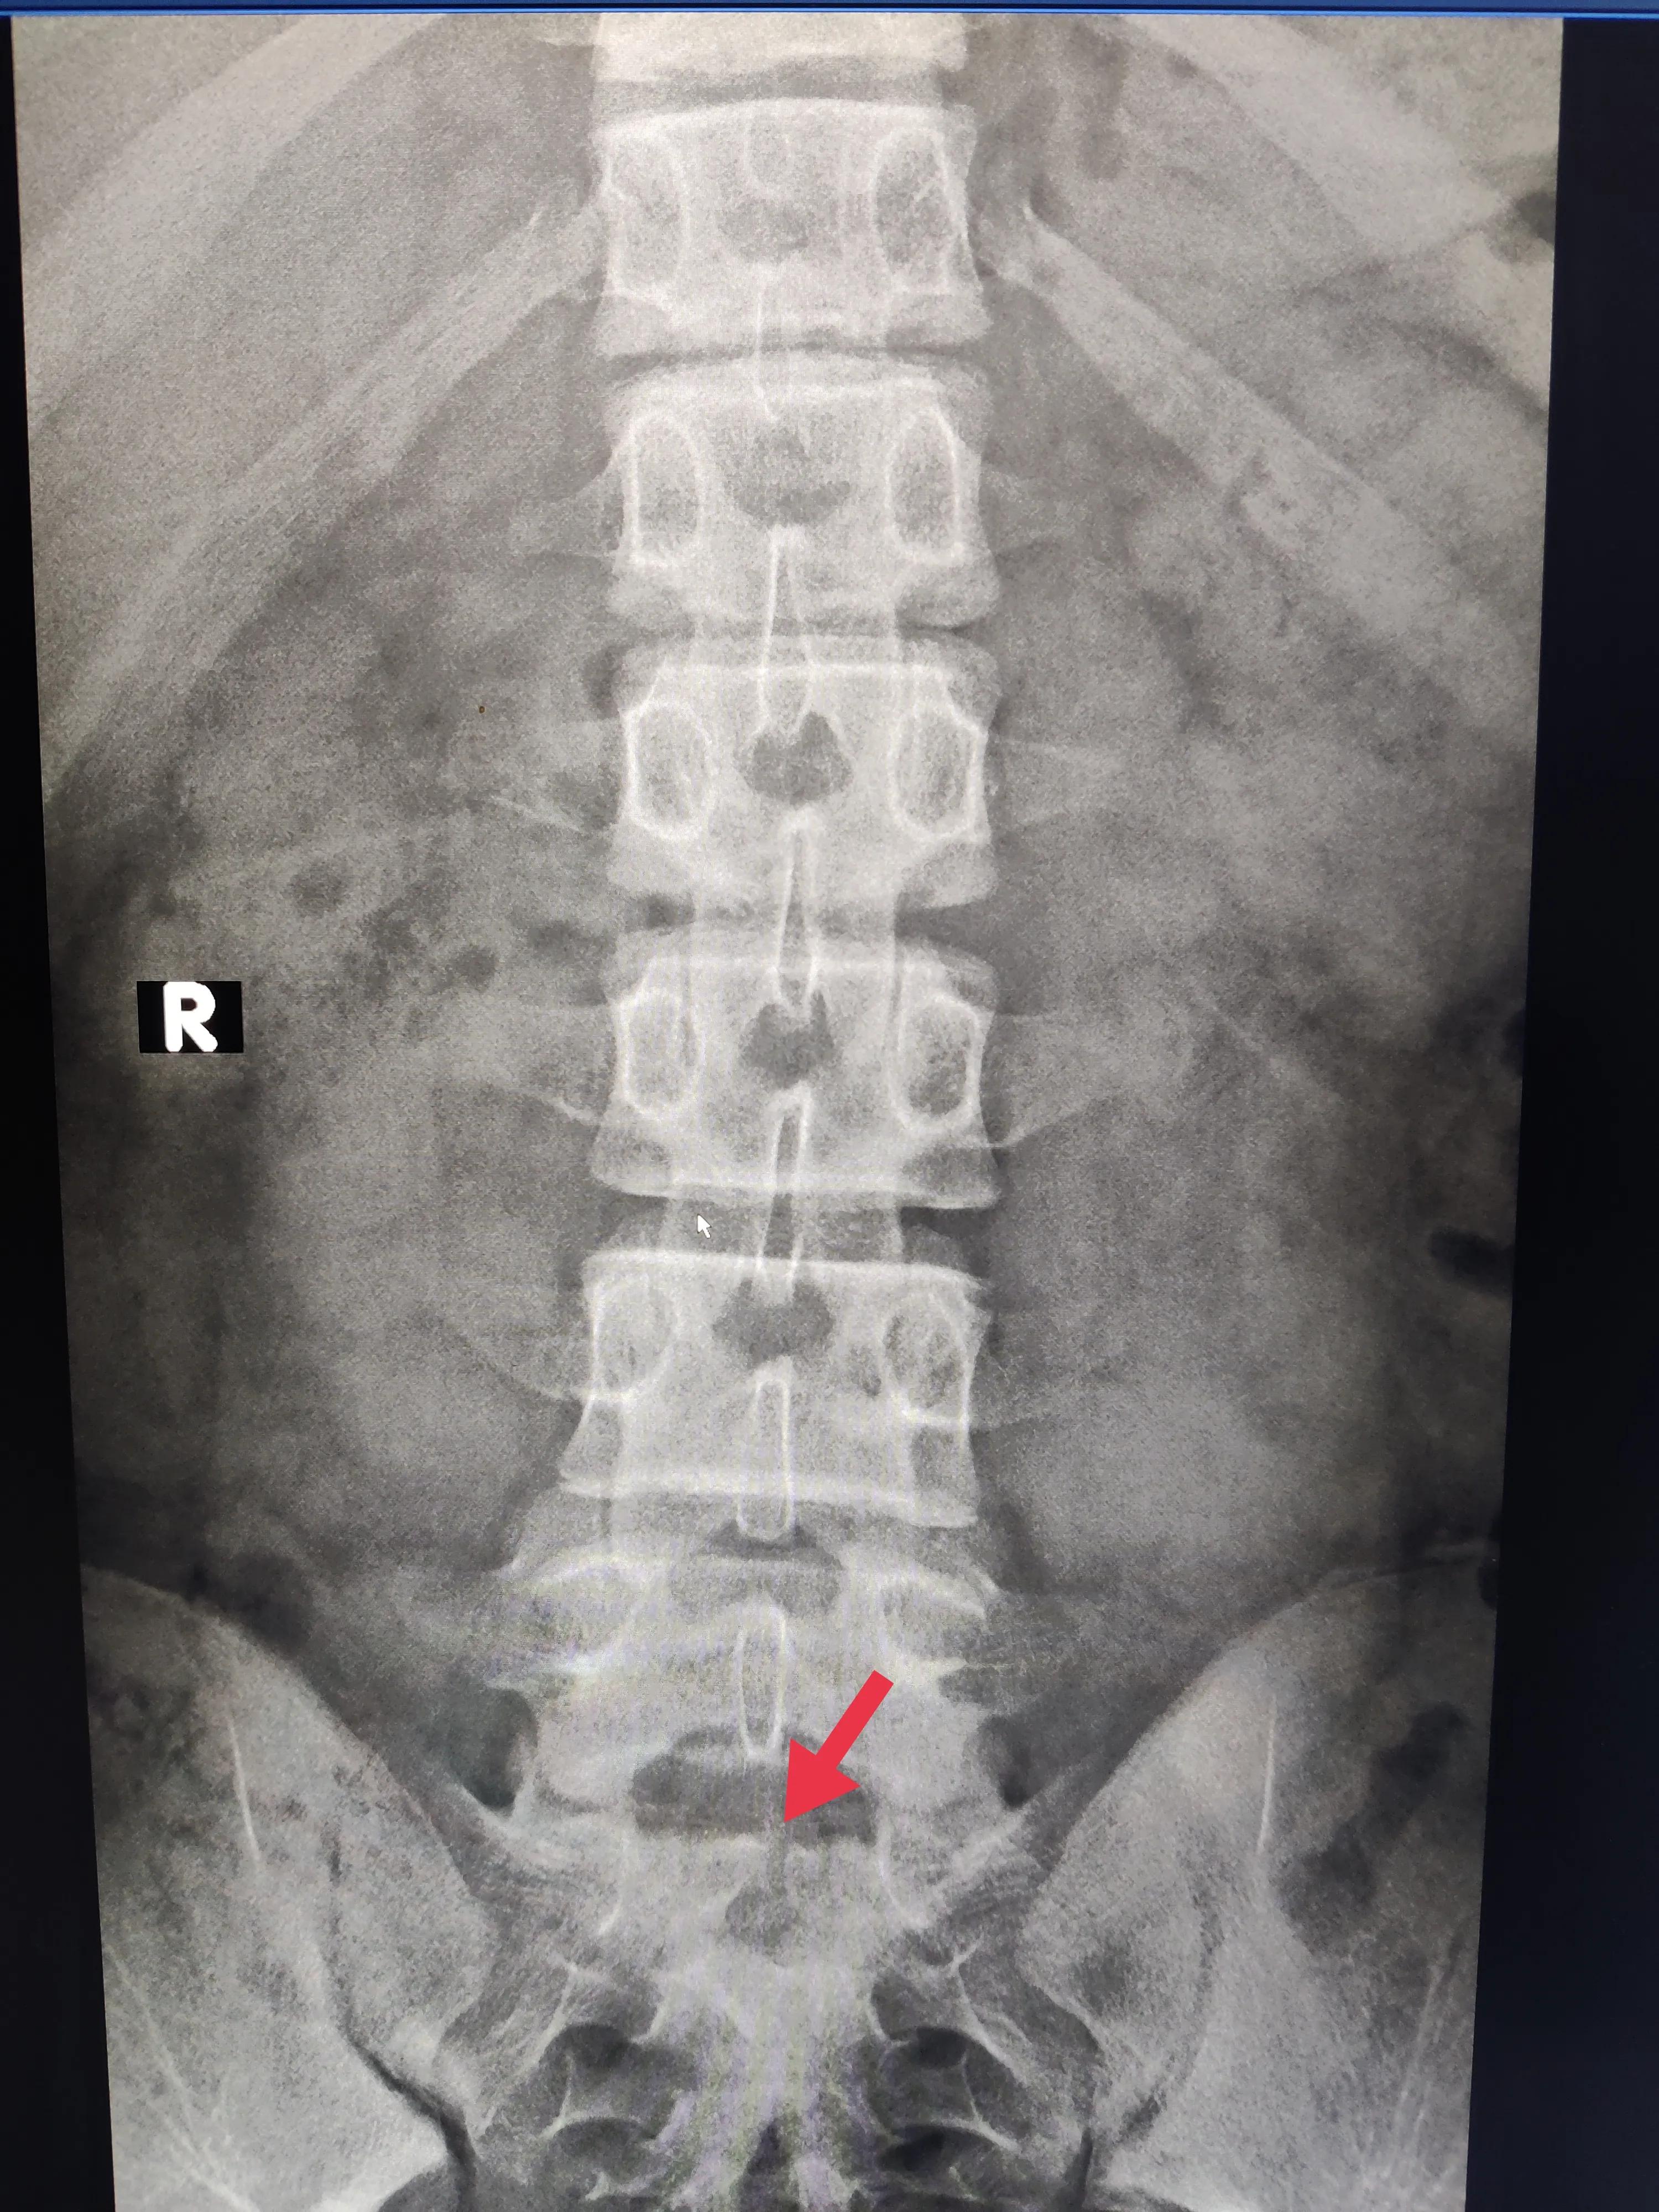

骶1椎体隐形骶裂